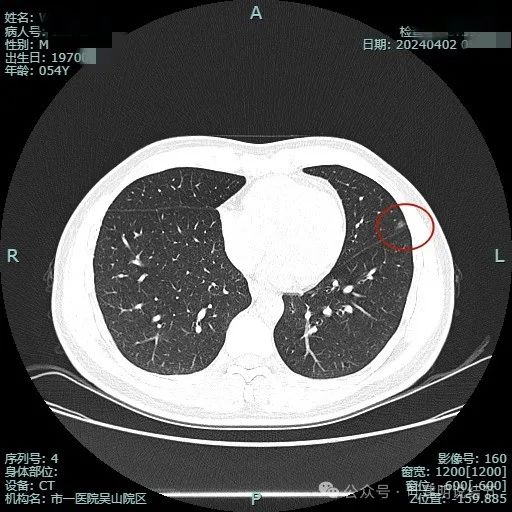

2024年4月复查影像:

病灶大小没有什么变化,当然也没有吸收好转。

病灶连续略显毛刺感。

关键是上图层面怎么贴着叶间裂这侧密度有增高了?偏实性成分!2023年3月时是靶重建情况下都没有见到偏实性成分的。